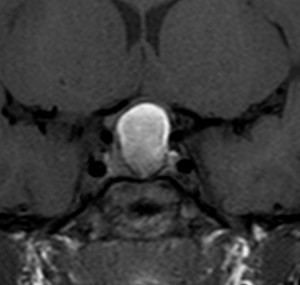

成人の第3脳室内部に局在する頭蓋咽頭腫です。経脳梁法で両側のモンロー孔から全摘出しました。下垂体組織は残っています。これは乳頭状頭蓋咽頭腫と呼ばれるもので,成人にしか発生しません,のう胞がなく石灰化もないのが大きな特徴です。境界が明瞭で柔らかく摘出が簡単なタイプとして知られています。この患者さんも術後に下垂体機能不全も視床下部障害も生じませんでした。